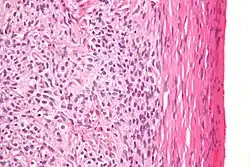

| Micrograph of a granulosa cell tumour, a type of sex-cord–gonadal stromal tumour. H&E stain. | |